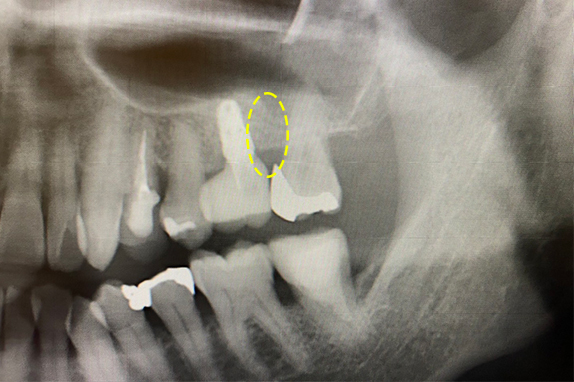

CASE 01 歯周再生治療

-

- 主訴

- 歯がグラグラで噛めない

-

- 回数期間

- 5回 約1年

-

- 治療法

- 歯周再生治療

-

- 治療費用

- 約17万円(税抜)

歯がグラグラで噛めないという主訴の患者様に歯周再生治療を用いて改善したケースです。レントゲン写真をみると術前は歯肉の退縮が見られるが、術後は歯肉の退縮が改善しています。

<リスク・副作用>

手術後は腫れ、痛み、痺れなどの副作用が生じる場合があります。